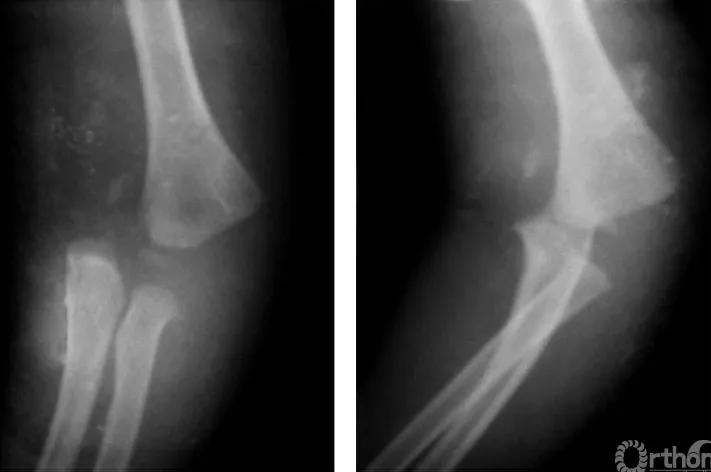

二、尺偏型

例:见肱骨小头及滑车骨骺伴前臂骨一同移向肘之尺侧,并略有旋转(图2)。

图2